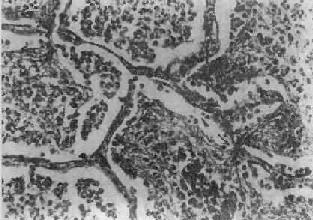

图9-19 支气管肺炎 图中见灶状实变的肺组织,肺泡内充满以中性粒细胞为主的炎性渗出物;病灶中有发炎的细支气管 【并发症】 小叶性肺炎发生并发症的危险性比大叶性肺炎大得多。可并发心力衰竭、呼吸衰竭、脓毒败血症、肺脓肿及脓胸等。支气管破坏较重且病程较长者,可导致支气管扩张。 【临床病理联系】 因小叶性肺炎多为其他疾病的并发症,其临床症状常为原发性疾病所掩盖。由于支气管粘膜的炎症刺激而引起咳嗽,痰呈粘液脓性。因病变常呈灶性散布,肺实变体征一般不明显。病变区细支管和肺泡内含有渗出物,听诊可闻湿啰音。X线检查,可见肺野内散在不规则小片状或斑点状模糊阴影。本病发现及时,治疗得当,肺内渗出物可完全吸收而痊愈。但在幼儿,年老体弱者,特别是并发于其他严重疾病时,预后大多不良。 (二)病毒性肺炎 病毒性肺炎(viral pneumonia)常常是因上呼吸道病毒感染向下蔓延所致。患者多为儿童,症状轻、重不等,但婴幼儿和老年患者病情较重。一般多为散发,偶可酿成流行。引起肺炎的病毒种类较多,常见的是流感病毒、还有呼吸道合胞病毒、腺病毒、副流感病毒、麻疹病毒、巨细胞病毒等等,也可由一种以上病毒混合感染并可继发细菌感染。病毒性肺炎的病情、病变类型及其严重程度常有很大差别。 【病理变化】 早期或轻型病毒性肺炎表现为间质性肺炎,炎症从支气管、细支气管开始,沿肺间质发展,支气管、细支气管壁及其周围、小叶间隔以及肺泡壁等肺间质充血、水肿,有一些淋巴细胞和单核细胞浸润,肺泡壁明显增宽(图9-20)。肺泡腔内一般无渗出物或仅有少量浆液。病变较重者,肺泡也可受累,出现由浆液、少量纤维蛋白、红细胞及巨噬细胞组成的炎性渗出物,甚至可发生组织坏死。有些病毒性肺炎(如流感病毒肺炎,麻疹病毒肺炎、腺病毒肺炎等)肺泡腔内渗出较明显,渗出物浓缩凝结成一层红染的膜样物贴附于肺泡内表面,即透明膜形成。支气管上皮的肺泡上皮也可增生,甚至形成多核巨细胞。麻疹病毒肺炎的病变特点为在间质性肺炎的基础上,肺泡壁上有透明膜形成,并有较多的多核巨细胞(巨细胞肺炎),在增生的上皮细胞和多核巨细胞的胞浆内和胞核内可检见病毒包含体。病毒包含体常呈球形,约红细胞大小,呈嗜酸性染色,均质或细颗粒状,其周围常有一清晰的透明晕。其他一些病毒性肺炎也可在增生的支气管上皮、支气管粘液腺上皮或肺泡上皮细胞内检见病毒包含体。如腺病毒肺炎可在增生的上皮细胞核内(图9-21),呼吸道合胞病毒肺炎可在增生的上皮细胞胞浆内,巨细胞病毒肺炎也可在增生的上皮细胞核内检见病毒包含体。检见包含体是病理组织学诊断病毒性肺炎的重要依据。

图9-20 间质性肺炎 肺泡壁及细支气管周围肺间质内有大量炎性细胞(主为单核细胞)浸润。肺泡壁明显增宽。肺泡腔内无渗出物